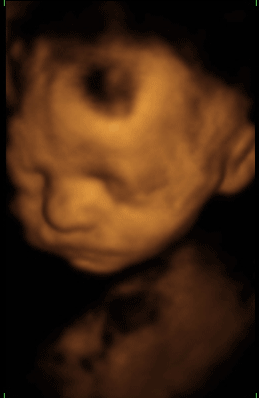

Vea que también los fetos tienen cara de mal genio. Pueden observar perfectamente el tórax y parte del abdomen. ¡Ojo!, la sombra en la cabeza no es el pelo, es un efecto extraño que hacen los ultrasonidos.